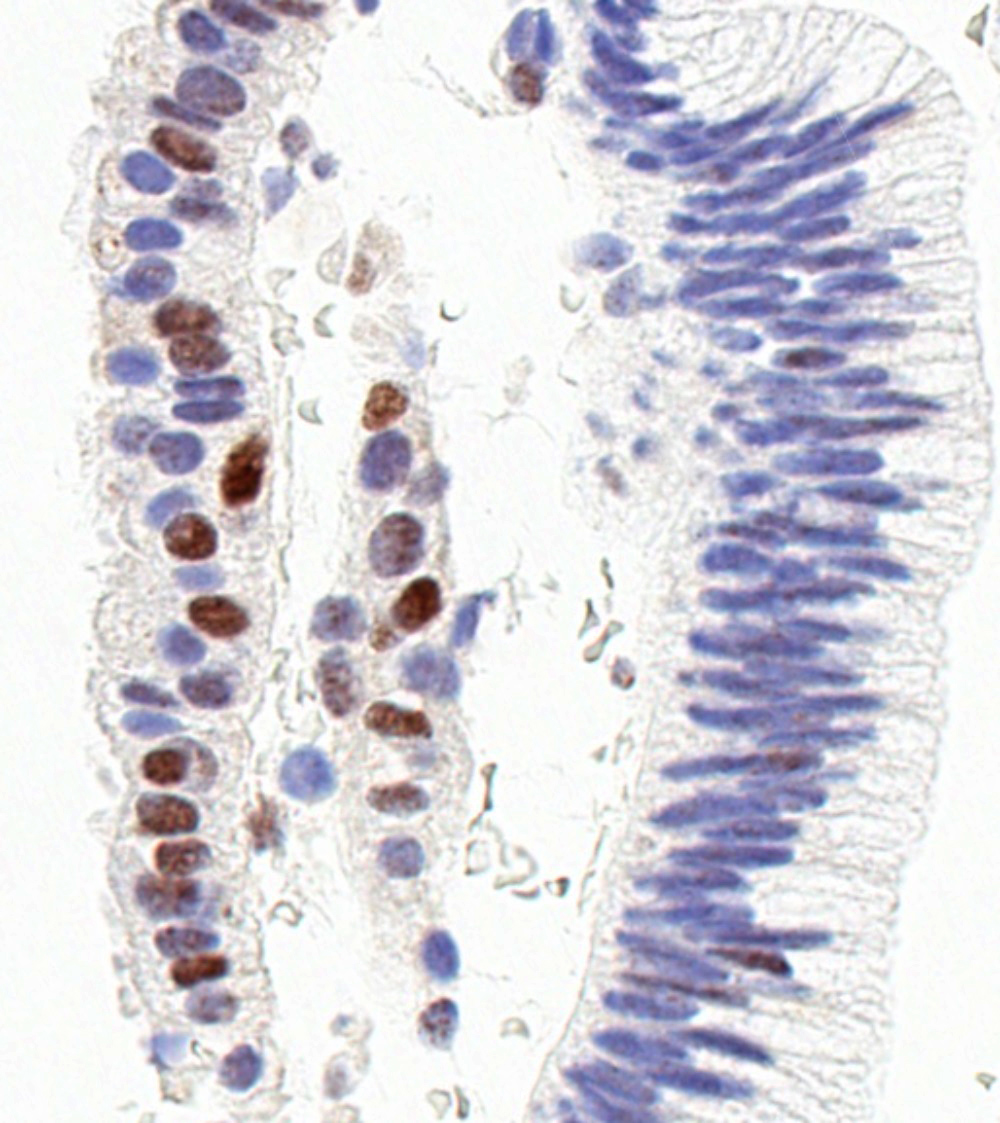

Microscopic (histologic) images

Contributed by Jessica L. Bentz, M.D.

Positive stains

- Morular metaplasia:

- CD10, CDX2, SATB2, beta catenin (nuclear and cytoplasmic)

- Tubal metaplasia (Mod Pathol 2011;24:1254):

- Resembling fallopian tube epithelium; pseudostratified with ciliated eosinophilic cells and clear round cells